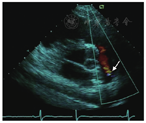

(1)胸骨旁肺动脉长轴切面对诊断肺动脉瓣病变(观察有无瓣膜狭窄、反流、赘生物等),主肺动脉和左、右肺动脉病变以及动脉导管未闭(PDA)有重要价值。例6:动脉导管未闭(图7,视频7)。

(2)根据肺动脉瓣反流压差估测肺动脉舒张压(DPAP)和平均压(MPAP)。舒张早期跨瓣压差估测肺动脉平均压;舒张晚期跨瓣压差估测肺动脉舒张末压,见图8。

注:VearlyPR舒张早期肺动脉瓣反流速度;VendPR舒张末期肺动脉瓣反流速度;RAP右心房压;DPAP肺动脉舒张压;MPAP肺动脉平均舒张压;MPAP=4(VearlyPR)2+RAP,DPAP=4(VendPR)2+RAP

(3)诊断和评估肺栓塞的重要切面之一,见图9。